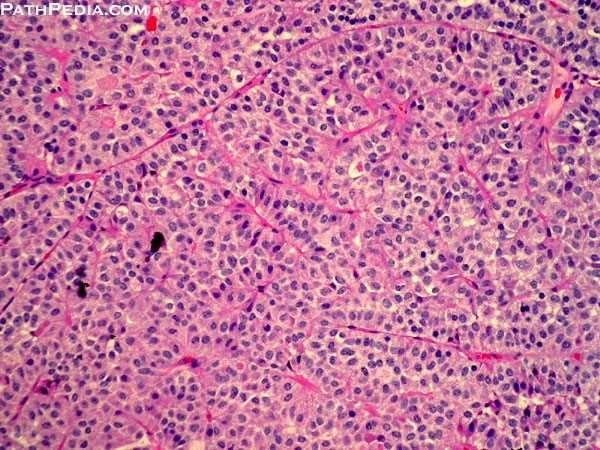

A benign, well-circumscribed, soft lesion of the pituitary gland that may compress the optic chiasm and adjacent structures. Composed of relatively uniform, polygonal cells arrayed in sheets, cords, or papillae.

Pituitary adenoma (TOPNOTCH)Robbins Basic Pathology, 8th ed., p. 754